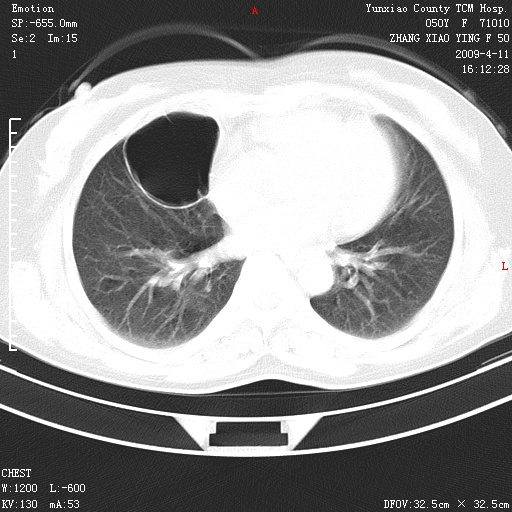

标题: CT19324:胸闷1周伴咳嗽 [打印本页]

标题: CT19324:胸闷1周伴咳嗽

肺囊肿并感染。

胸膜下肺大泡

病灶周围肺纹受压移位走行较柔和,余肺里实质均匀,纹理如常,肺间质无显著纤维化,支持考虑孤立性肺囊肿

先天性肺气囊肿!

考虑右肺中叶肺囊肿。